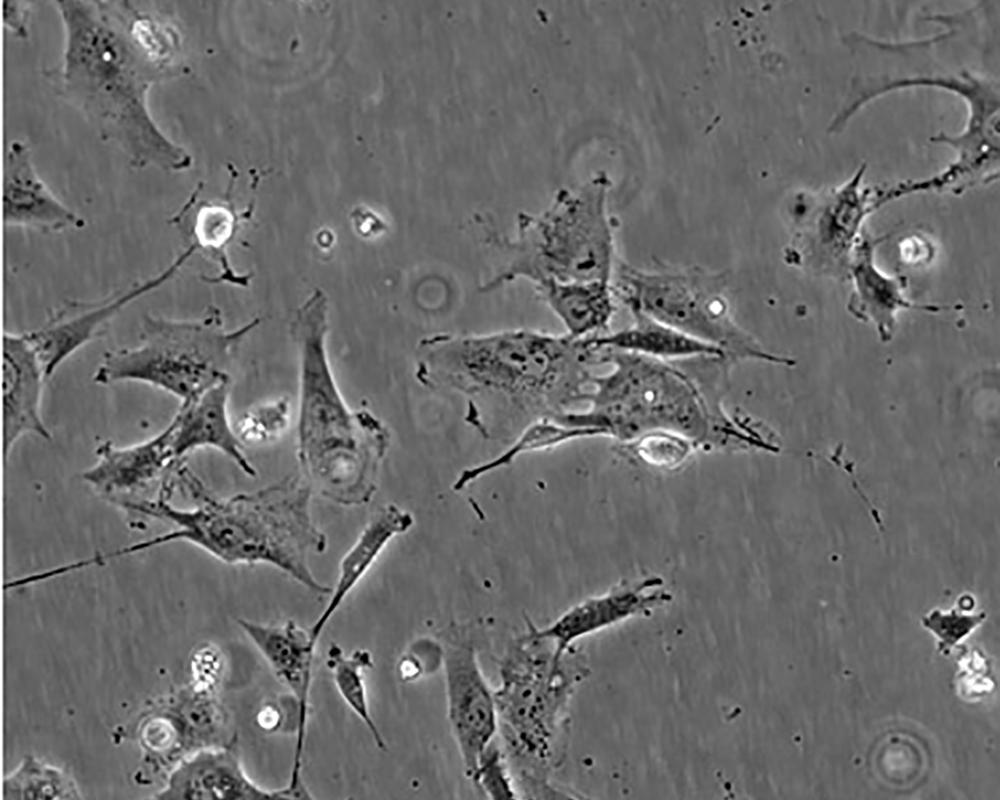

細胞描述 The Hs 578T line had a mixed polygonal morphology initially, but a stellate cell type was selected for during passage and by cloning. Aggregates of casein protein granules, desmosomes, tight junctions, lipid droplets and vesicularized smooth endoplasmic reticulum were observed by electron microscopy. As with Hs 578Bst, no estrogen receptors or endogenous viruses were detected.